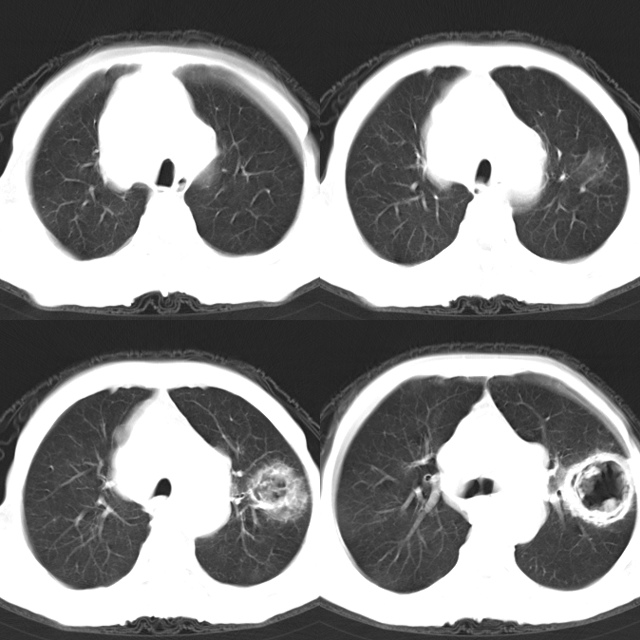

以下是引用心路寻觅在2010-4-17 18:35:00的发言:[br]纵膈多组淋巴结肿大呈“冰冻纵膈”,左肺上叶空洞伴其内结节密度影,考虑淋巴瘤伴左肺上叶曲霉菌感染。[br][br][本贴已被 心路寻觅 于 2010-4-17 18:36:23 修改过]

以下是引用zhangzhongshou在2010-4-17 19:32:00的发言:[br]一元论考虑左肺空洞型肺癌并纵隔淋巴结转移可能性大。